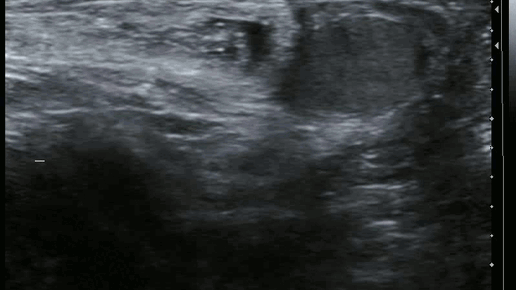

Около 3% мужчин встречаются с таким неприятным явлением как паховая грыжа. Она возникает также и у женщин, но несколько реже. Паховая область является слабым местом передней брюшной стенки, через естественные отверстия которого проходит семенной канатик у мужчин и круглая связка матки у женщин. Под действием различных факторов - анатомические особенности, слабость соединительной ткани, резкое поднятие тяжестей происходит выход различных органов живота через эти слабые места наружу, что проявляется выпячиванием - грыжей...